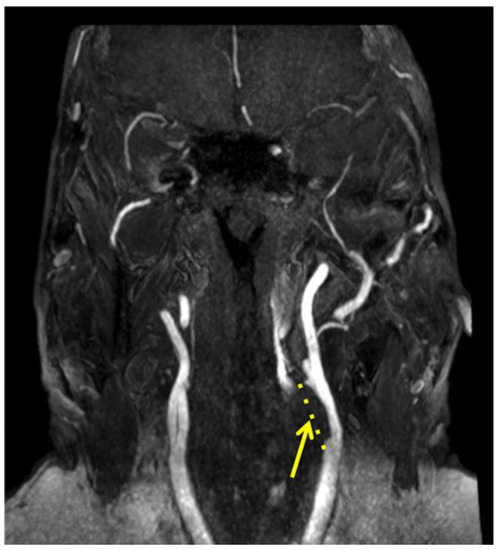

3. Computed Tomography Angiography (CTA) and Magnetic Resonance Angiography (MRA)

- Kerwin, W.S.; Hatsukami, T.; Yuan, C.; Zhao, X.Q. MRI of carotid atherosclerosis. AJR Am. J. Roentgenol. 2013, 200, W304–W313. [Google Scholar] [CrossRef]

- Demarco, J.K.; Ota, H.; Underhill, H.R.; Zhu, D.C.; Reeves, M.J.; Potchen, M.J.; Majid, A.; Collar, A.; Talsma, J.A.; Potru, S.; et al. MR carotid plaque imaging and contrast-enhanced MR angiography identifies lesions associated with recent ipsilateral thromboembolic symptoms: An in vivo study at 3T. AJNR Am. J. Neuroradiol. 2010, 31, 1395–1402. [Google Scholar] [CrossRef]

- Qiao, Y.; Etesami, M.; Malhotra, S.; Astor, B.C.; Virmani, R.; Kolodgie, F.D.; Trout, H.H.; Wasserman, B.A. Identification of intraplaque hemorrhage on MR angiography images: A comparison of contrast-enhanced mask and time-of-flight techniques. AJNR Am. J. Neuroradiol. 2011, 32, 454–459. [Google Scholar] [CrossRef]

- Deng, F.; Mu, C.; Yang, L.; Li, H.; Xiang, X.; Li, K.; Yang, Q. Carotid plaque magnetic resonance imaging and recurrent stroke risk: A systematic review and meta-analysis. Medicine 2020, 99, e19377. [Google Scholar] [CrossRef] [PubMed]